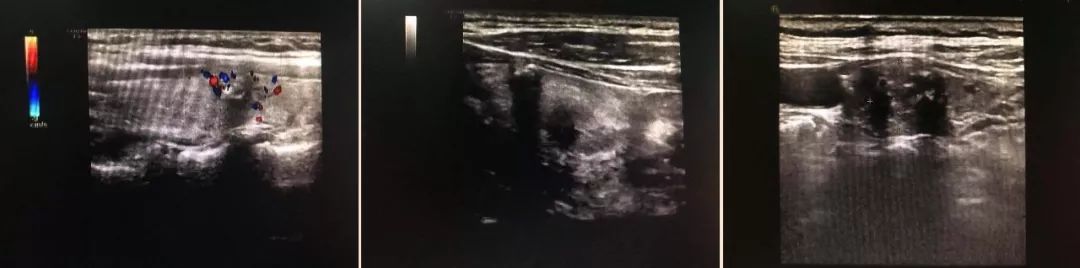

1、彩超

超声检查在甲状腺癌诊断体系中不可或缺以往有经验的超声医生鉴别甲状腺结节良恶性的准确率高达 85%。

恶性结节典型的超声特征包括:显著低回声、微小钙化、边缘不规则、纵径>横径、血供丰富、可疑淋巴结。

(医院彩超室提供)